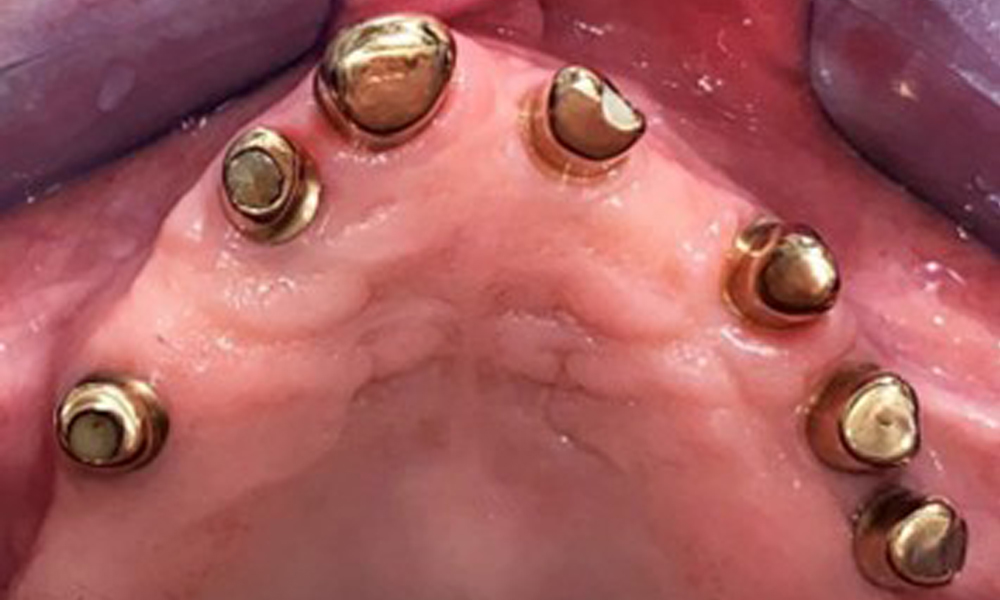

The dental findings are as follows: Combined removable implant and tooth-supported telescopic prostheses on implants 15, 13, 21, 23, 24, 25 and tooth 11 (Fig. 1, Fig. 2, Fig. 3). The patient was fitted with a fixed mandibular denture. Adequate bridges were present over 37 to 34 and 45 to 47 (Fig. 4), the crown margins were intact and there were no active caries. A composite filling with a marginal gap was present on tooth 43. There was mandibular gingival recession, exposing 1 to 3 mm of root surface. This also applies to 11.

Occlusal view: Maxilla with removable, palateless denture.

Fig. 3: Occlusal view: Maxilla with removable, palateless denture.